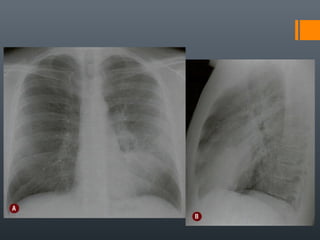

O documento discute vários conceitos radiológicos incluindo consolidação, atelectasia, nódulos, pseudocavidades e padrões intersticiais, fornecendo definições, sinais e diagnósticos diferenciais para cada tópico. Ele também discute a redução da atenuação pulmonar e fornece um link para mais informações.